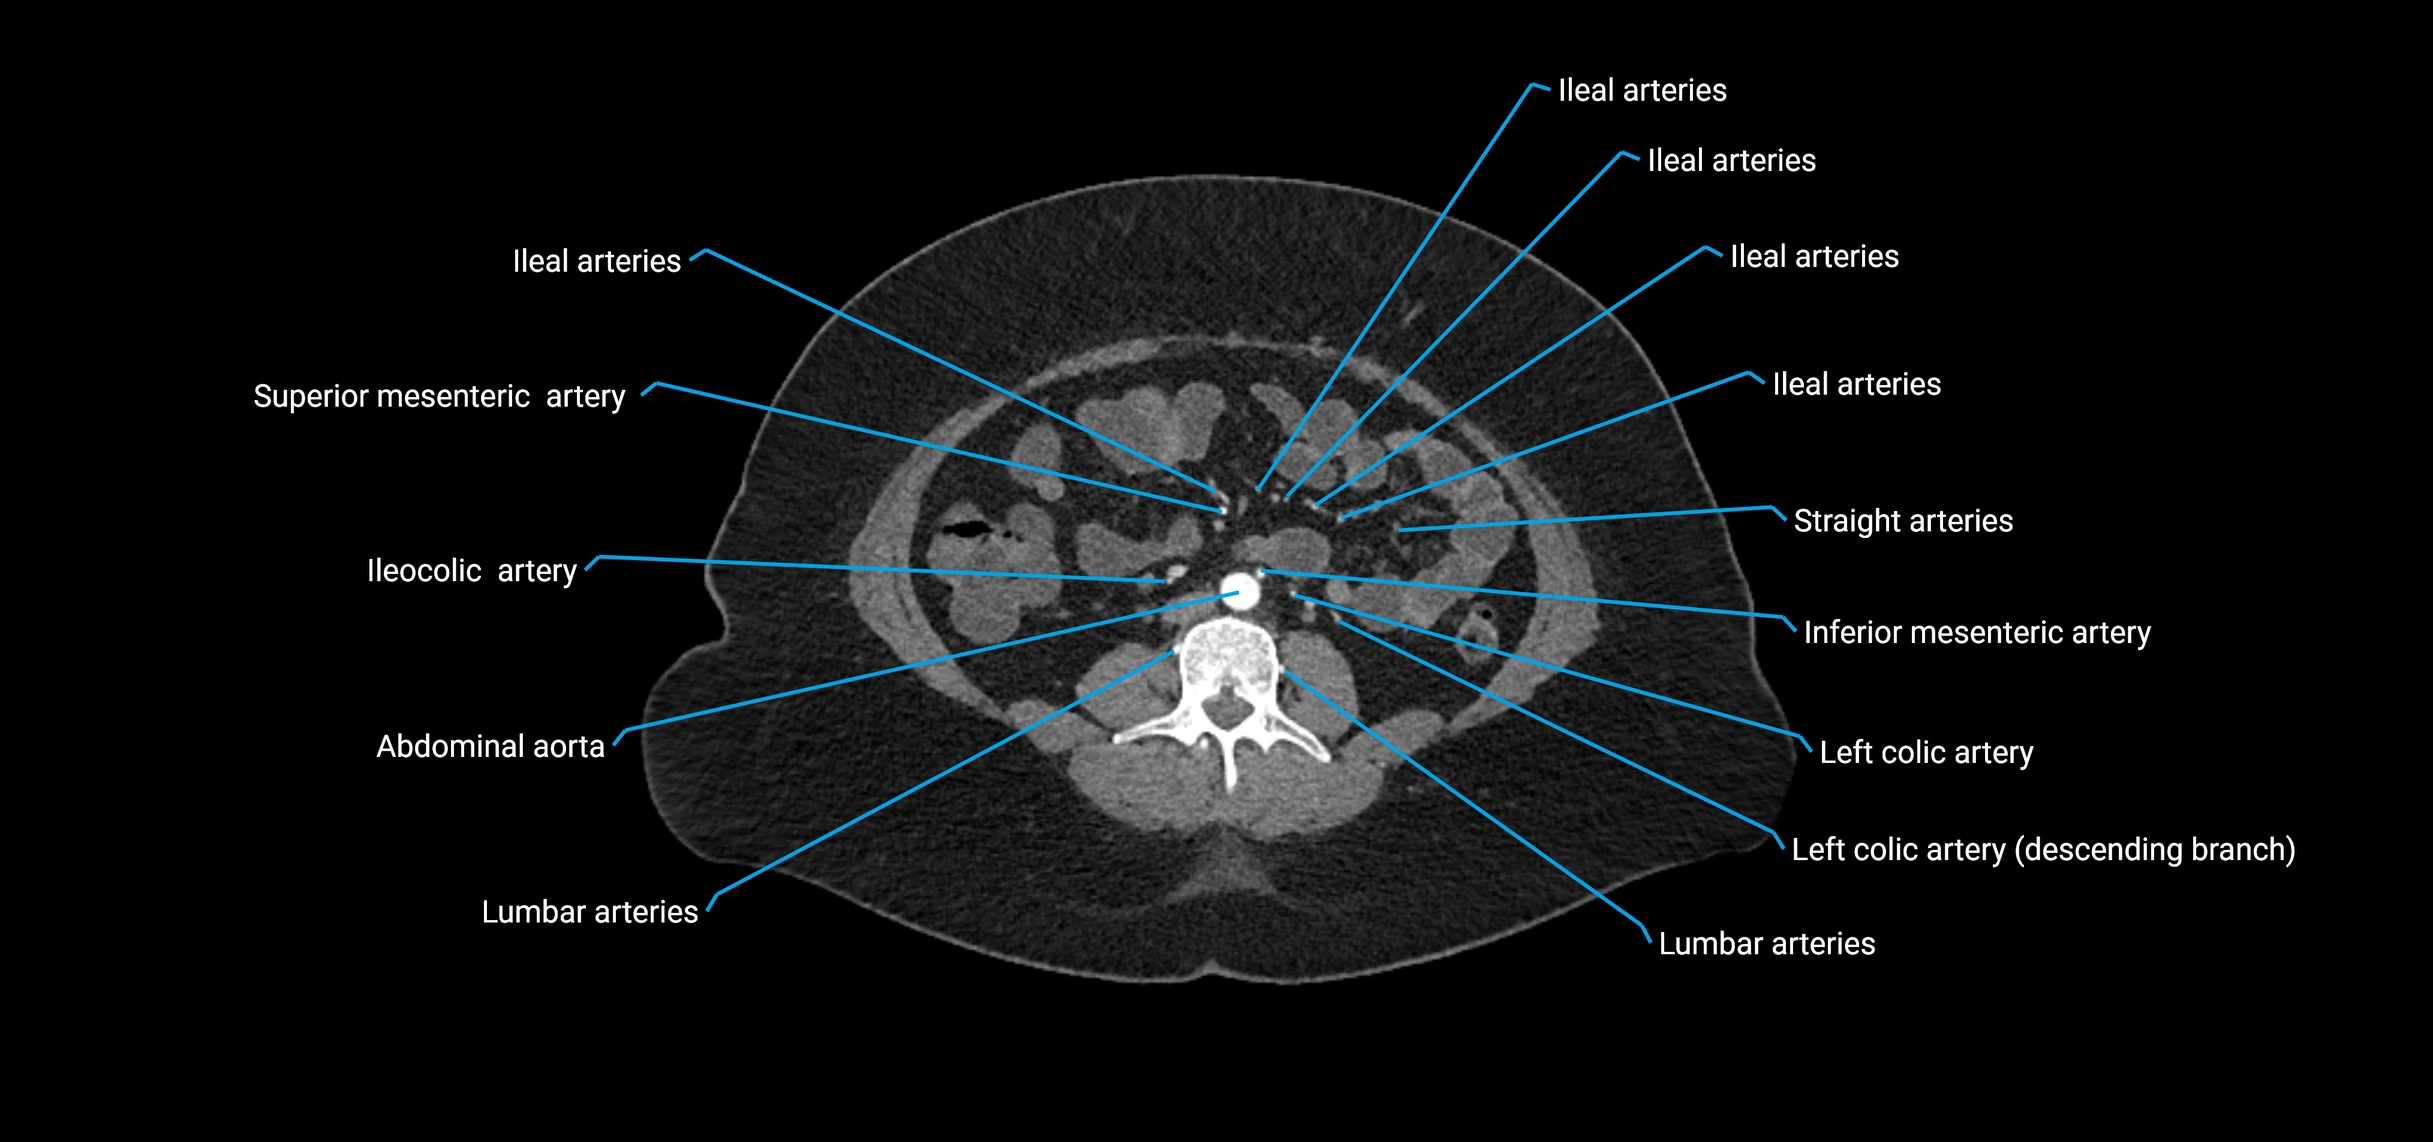

CT images

image

Contrast-enhanced CT (CTA):

• Gold standard for abdominal aortic imaging

• Provides excellent detail of lumen, wall, aneurysm, thrombus, and branch vessels

• Multiplanar and 3D reconstructions help in aneurysm measurement, stent graft planning, and dissection evaluation